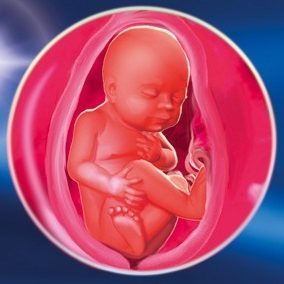

Плід на 26 тижні вагітності

На даному терміні вагітності плід вже має ті особливі риси, які будуть характерні йому в майбутньому. Брови, вії вже розташовуються на відведених для них місцях, вже сформовані трохи відстовбурчуються від голови вуха, сформована структура внутрішнього вуха, що дозволяє маляті відмінно чути не тільки звуки усередині материнського живота, але і зовні. В цей же час починають поступово відкриватися очі, тому слід уникати яскравого освітлення і надмірно гучних звуків, щоб не нашкодити ще зовсім беззахисним системам плода. Набагато краще періодично радувати дитинку своїм ніжним голосом, наспівуючи пісеньки, або слухаючи класичну музику. Плід на 26 тижні вагітності вже вміє розрізняти голоси мами і тата, що вкрай сприятливо відбивається на процесах його розвитку.

Двадцять шостий тиждень вагітності характеризується подальшим зміцненням кісткової тканини дитини, закінченням формування зачатки зубів і дихальної системи. У цей час легені знаходять закінченого вигляду і розташовуються у відведеному для них місці, а значить, малюк вже здатний до нормальних дихальним процесам відразу ж після розставання з животом мами.

Потихеньку відбувається зміна кольору шкіри плода, вона розгладжується, кінцівки округлюються, а там де, повинні бути лікті, утворюються складочки. До цього моменту мозок дитинку вже пов'язаний з корою наднирників, в результаті чого відбувається вироблення гормону росту і ряду інших гормонів.

Говорячи про те, що відбувається з малюком на 26 тижні вагітності, необхідно відзначити і його основні параметри: вага досягає приблизно 750 г, зріст - 35,5 см. Він спить майже 20 годин на добу, а решту часу присвячує різним рухам і ворушінню. При цьому за всім цим вже можуть спостерігати оточуючі, так як місця в животі вже недостатньо і все ворушіння відчутні не тільки самої вагітної, а й легко виявляються на поверхні її живота усіма домочадцями.

Фото плода на 26 тижні вагітності: